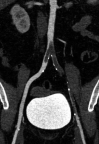

Results: During the study period, 424 patients underwent 499 arterial duplex, computed tomography angiogram, or magnetic resonance angiography imaging studies with an overall 9.4% positive rate for arterial thromboembolism. Of the 40 patients with arterial thromboembolism, 25 (62.5%) were SARS-CoV-2 negative or admitted for unrelated reasons and 15 (37.5%) were SARS-CoV-2 positive. The odds ratio for arterial thrombosis in COVID-19 was 3.37 (95% confidence interval, 1.68-6.78; P = .001). Although not statistically significant, in patients with arterial thromboembolism, patients who were SARS-CoV-2 positive compared with those testing negative or not tested tended to be male (66.7% vs 40.0%; P = .191), have a less frequent history of former or active smoking (42.9% vs 68.0%; P = .233) and have a higher white blood cell count (14.5 vs 9.9; P = .208). Although the SARS-CoV-2 positive patients trended toward a higher the neutrophil-to-lymphocyte ratio (8.9 vs 4.1; P = .134), creatinine phosphokinase level (359.0 vs 144.5; P = .667), C-reactive protein level (24.2 vs 13.8; P = .627), lactate dehydrogenase level (576.5 vs 338.0; P = .313), and ferritin level (974.0 vs 412.0; P = .47), these differences did not reach statistical significance. Patients with arterial thromboembolic complications and SARS-CoV-2 positive when compared with SARS-CoV-2 negative or admitted for unrelated reasons were younger (64 vs 70 years; P = .027), had a significantly higher body mass index (32.6 vs 25.5; P = .012), a higher d-dimer at the time of imaging (17.3 vs 1.8; P = .038), a higher average in hospital d-dimer (8.5 vs 2.0; P = .038), a greater distribution of patients with clot in the aortoiliac location (5 vs 1; P = .040), less prior use of any antiplatelet medication (21.4% vs 62.5%; P = .035), and a higher mortality rate (40.0% vs 8.0%; P = .041). Treatment of arterial thromboembolic disease in COVID-19 positive patients included open thromboembolectomy in six patients (40%), anticoagulation alone in four (26.7%), and five (33.3%) did not require or their overall illness severity precluded additional treatment.

Conclusions: Patients with SARS-CoV-2 are at risk for acute arterial thromboembolic complications despite a lack of conventional risk factors. A hyperinflammatory state may be responsible for this phenomenon with a preponderance for aortoiliac involvement. These findings provide an early characterization of arterial thromboembolic disease in SARS-CoV-2 patients.